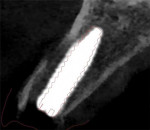

Once the integrity of the socket was verified, the previously fabricated 3D printed surgical guide was inserted, and complete seating was verified via the occlusal cutout on the first premolar and the incisal cutouts on the canine and central incisors (Figure 16). Osteotomy burs and guide sleeves (Guided Surgery Kit, BioHorizons) were then used to develop the site to accommodate a 3.3 mm × 16 mm implant (CONELOG®, BioHorizons) (Figure 17). Following completion of the osteotomy, the site was debrided with 5 mL of a 0.5 mg metronidazole solution. The implant was then placed through the surgical guide to ensure that the planned depth was achieved, which would ensure that the 3D printed immediate provisional restoration would be positioned where planned (Figure 18). After the implant was placed, its initial stability was evaluated using resonance frequency analysis (Osstell® ISQ, Osstell). It was found to have an implant stability quotient of 75; therefore, immediate provisionalization was indicated.

Following radiographic evaluation of the implant position, the cover screw was removed, and the 3D printed screw-retained provisional restoration was inserted (Figure 22). The fixation screw was hand tightened so as not to turn the implant. To verify complete seating of the titanium base in the implant, a periapical radiograph was acquired (Figure 23). Sterilized PTFE tape was then placed into the access hole over the fixation screw, and the access was sealed with composite (Venus® Pearl, Kulzer) and light cured. Once the provisional restoration was placed, the occlusion was checked to confirm that there were no contacts in any position and adjusted as needed. The esthetics of the 3D printed provisional restoration allowed it to blend well with the adjacent dentition (Figure 24).